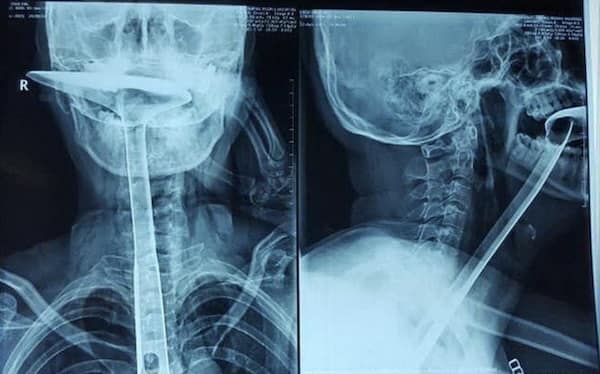

I used to think that nothing could surprise me anymore—until I stumbled upon some weird x-ray photos that made me reconsider my stance on human ingenuity (or lack thereof). Apparently, some people have a knack for getting objects lodged where they absolutely shouldn’t be. If you’ve ever wondered how not to use everyday items, these images might provide some unintended guidance.

This collection showcases 31 bizarre x-ray images that defy logic and anatomy textbooks alike. Each photo reveals unexpected objects making cameo appearances inside the human body, turning medical imaging into a gallery of the absurd. From common household items inexplicably found in unusual places to anomalies that would leave even seasoned doctors scratching their heads, these images offer a perplexing glimpse into the more “creative” side of medical emergencies. They highlight the intersection of curiosity, misadventure, and perhaps a dash of poor decision-making, all captured through the lens of radiology.